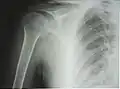

К 4—6 годам указанные центры сливаются в единую головку плечевой кости. Замещение метаэпифизарного хряща на границе проксимального эпифиза и диафиза костной тканью (синостоз) наступает в подростковом возрасте, благодаря чему продолжается рост кости в длину. На рентгенограмме ребёнка или подростка определяется характерный светлый участок на месте метаэпифизарного хряща, который может быть принят за перелом или трещину[4].

Рентгенограмма верхней части плечевой кости с выраженной хирургической шейкой